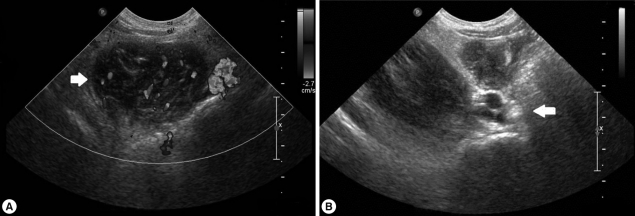

One month after the first admission, the eosinophil count in the peripheral blood and the total serum IgE value were still high (eosinophils, 37.4%; IgE, 1,094 IU/ml). The follow-up chest radiograph showed improvements of the left pleural effusion, but persistence of the right pleural effusion (Fig. 3A). She was, therefore, readmitted to the hospital, and the pleural fluid was drained using a pigtail catheter.

Analysis of the drained pleural fluid showed the following results: WBC, 250 cells/mm3 (neutrophils, 8%; lymphocytes, 49%); pH, 7.164; protein, 9.8 g/dl; albumin, 2.7 g/dl; glucose, 4 mg/dl; and amber colored appearance. Gram staining and culture studies of the pleural fluid were negative, but P. westermani-specific IgG antibody was strongly positive in the pleural fluid, with an OD of 1.576 (cut-off OD: 0.002). Abdominal sonography revealed a smaller, albeit still existing, inflammatory lesion in the right psoas muscle (Fig. 3B). The patient was treated again with a third cycle of praziquantel therapy. After 4 days, the catheter for draining pleural fluid was removed, and she was discharged.

The major symptoms of paragonimiasis are cough, hemoptysis, and dyspnea; some of these overlap with symptoms of tuberculosis and other pulmonary disorders. Pulmonary infiltrates, effusion, nodules, or lesions are also very common [14, 15], and ectopic locations of flukes include the pleura, abdominal wall, viscera, and brain. In our case, the patient complained of abdominal pain, especially in the right flank and right inguinal area but had no cough, dyspnea, or chest pain. The chest radiograph revealed pleural effusion, and abdominal sonography showed a low-echoic lesion with inflammation of the surrounding fat in the psoas mucle. This lesion is presumed to be due to adult flukes, which are present in loosely formed cysts in the psoas muscle.